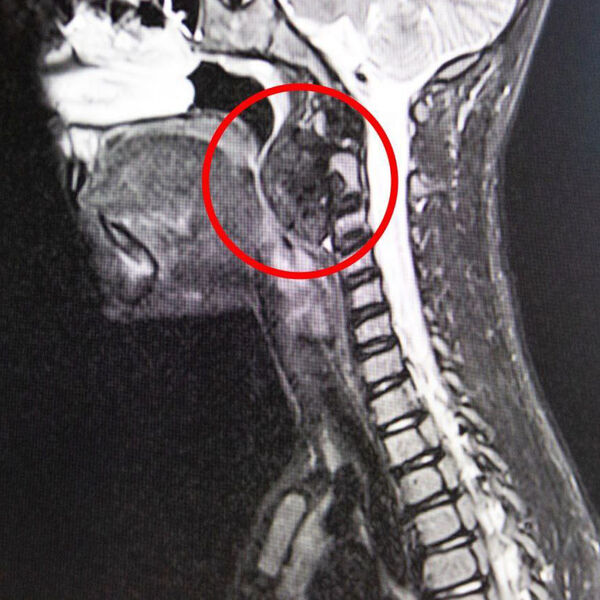

В Кемерове врачи удалили у девятилетнего мальчика опухоль в горле размером с яйцо

Родители маленького пациента рассказали, что ребенок начал задыхаться ночью во сне, испытывал сложности с глотанием во время приема пищи. В ходе обследования медики выявили в заглоточном пространстве гигантскую опухоль размером с куриной яйцо.

Было принято решение о хирургическом вмешательстве. Новообразование мешало пациенту дышать и сдавливало шейные позвонки.